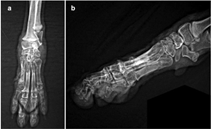

The management of metacarpal fractures can be either conservative, following a closed reduction and coaptation approach, or surgical where multiple techniques have been described including either internal or external fixation or a combination of both.6,7 To date, there is no consensus in the veterinary literature on which approach should be preferred.3 but general considerations when deciding the approach include the age of the animal, the type of the fractures, the extend of the bone and soft tissue damage, whether the fractures are open or closed, the presence of infection in old fractures and the concurrent presence of fractures in neighbouring bones.3‒6 In this case the closed reduction and coaptation technique was elected, as described by various authors for single or dual metacarpal fractures.4‒8 but modified due to fractures present on all metacarpals (Figure 1). The animal was placed on Sternal recumbency under deep anaesthesia. An Allis tissue forceps was placed on the nail of the 2nd digit and one on the nail of the 4th digit and the ends of the forceps were tied to a steady point on the wall via a traction rope in order to achieve better distribution of the traction force on all digits, whilst making certain that the limb and rope are on a straight line and exactly parallel to the table surface. Gentle and steady distal-to-proximal traction was applied on the limb with the surgeon’s left hand placed right proximally to the carpus while the right hand applied lateral-to-medial pressure on the metacarpal area in order to achieve axonal alignment. Under traction, a modified Robert-Jones splint was applied to provide stabilization. Postoperative radiographs showed good fracture reduction and alignment (Photo 2). Very strict rest was advised for 7days postoperatively and pain management was continued at home with carprofen at 4mg/kg orally once daily for 18 days. Gradual increase in exercise was advised after day 7 to encourage use of the limb and assist fracture healing. The splint was inspected on the 3rd and 12th day postoperatively for any signs of dressing complications such as vascular compromise of the limb or pressure-dermatitis, with no signs of complications. Conscious radiographs taken 18days postoperatively (Photo 3) revealed healing of the fractures and the animal was confident in using the limb with no indication of lameness. The splint was removed at day 20 and a small course of physiotherapy was followed for 2weeks due to moderate postoperative muscle atrophy. Follow-ups at 6 weeks and 3months after reduction, confirmed full recovery and return to normal activity.

Photo 2 Dorsopalmar radiograph after closed reduction.

Photo 3 Postoperative radiographs 18years after closed reduction. Dorsopalmar (a) and lateral (b) projections.